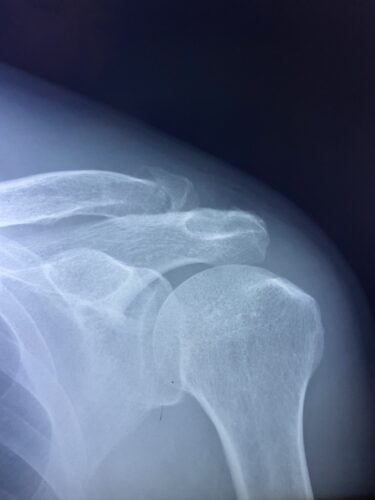

さわやか千葉県民プラザ(肩関節脱臼)